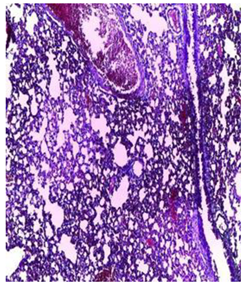

| Lung | ![]() | ![]() | ![]() |

| A pulmonary parenchyma, made of optically empty cavity (alveoli) separated by fibrous septa | Lung parenchyma seat of vascular congestion The vessels have a hyalinised wall with the presence of haemorrhagic diffusion. | Presence of vascular congestion Presence of lymphocytes inflammatory infiltrate | |